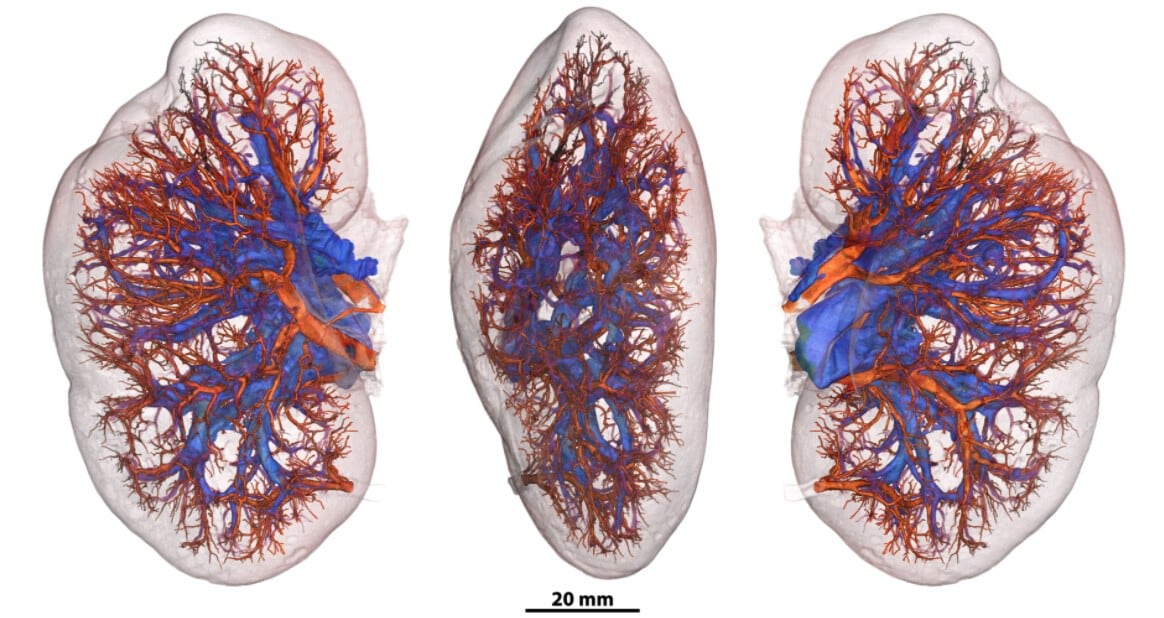

A diferencia de otros repositorios anatómicos, el Atlas de Órganos Humanos (HOA) ofrece acceso libre a imágenes tridimensionales de órganos humanos intactos. El portal ya permite explorar 65 órganos (de 13 tipos diferentes) procedentes de 32 donantes y 321 conjuntos de datos completos.

Los órganos disponibles incluyen cerebro, corazón, pulmón, riñón, hígado, útero, próstata, genitales femeninos, colon, bazo, placenta, ojo y testículos. Las muestras provienen de biobancos europeos como el Biobanco Unificado de Hannover o el Laboratorio de Anatomía de los Alpes Franceses.

El método HiP-CT ya permitió identificar lesiones vasculares microscópicas en pulmones de pacientes fallecidos por covid-19, redefinir la comprensión de trastornos cardíacos y aportar información inédita sobre la patogénesis de enfermedades ginecológicas y renales. “En el riñón descubrimos que los glomérulos no están todos al final de la red vascular, como se creía, sino distribuidos de forma completamente distinta”, señaló Walsh.

La plataforma incorpora herramientas de software para analizar y visualizar los órganos en el navegador, junto con galerías de imágenes, videos y recursos para descargar información en diferentes niveles de resolución. El equipo espera expandir el repositorio con más órganos, una mayor diversidad de donantes y nuevas funciones, a la vez que promueve la construcción de una comunidad global abierta y conectada. El objetivo a largo plazo es desarrollar la técnica para obtener imágenes de cuerpos humanos completos con una resolución 10 a 20 veces superior a la actual.